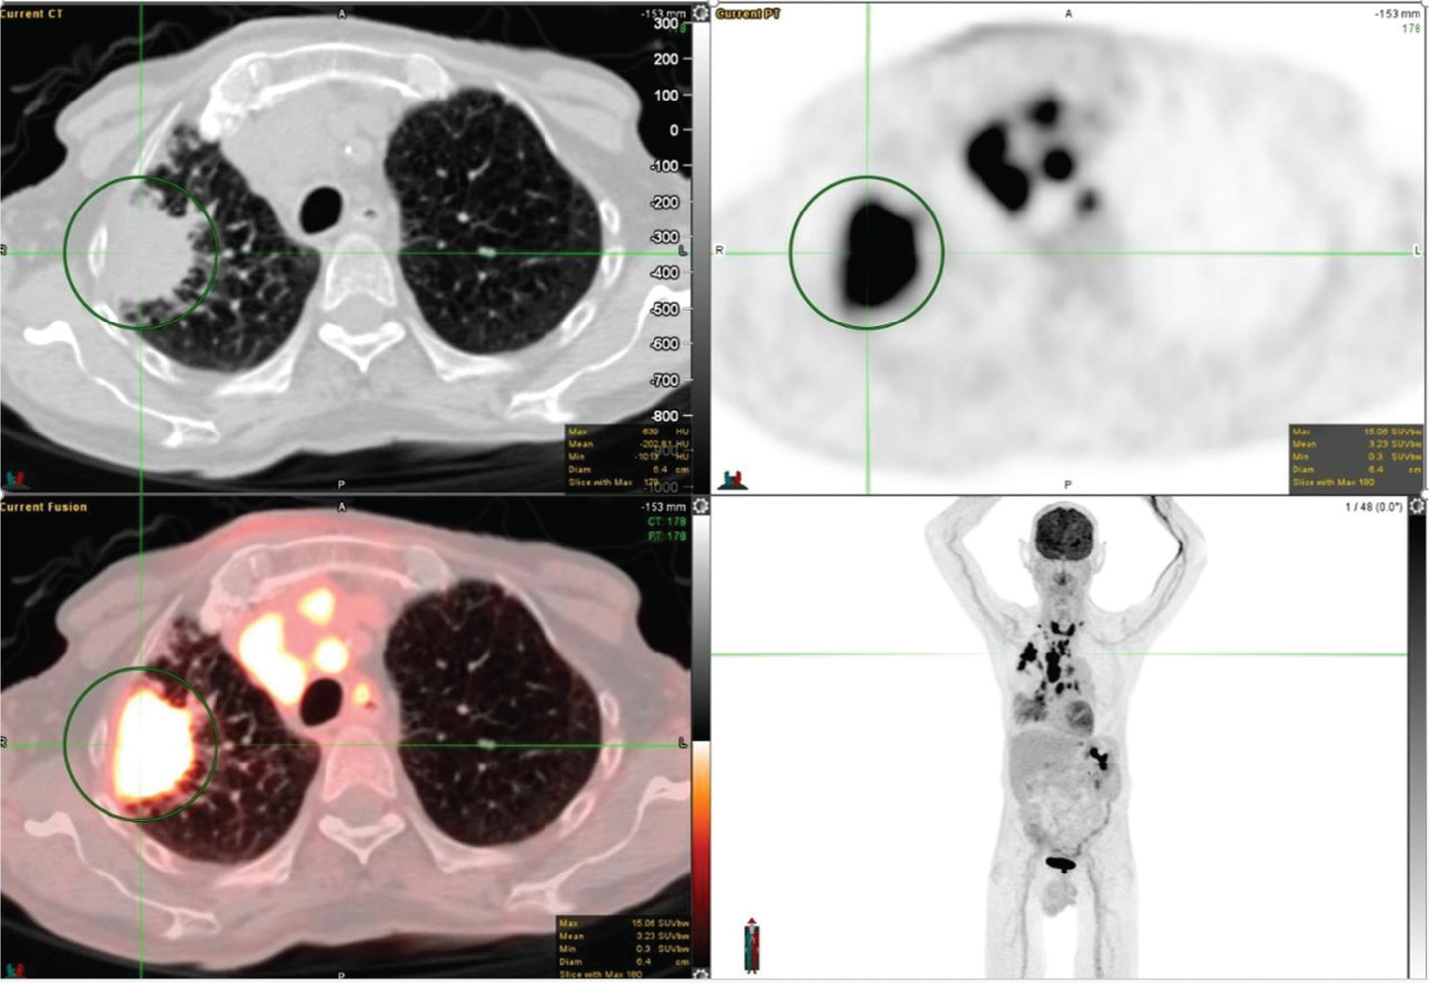

18F-FDG PET/CT has been widely studied for its use in the accurate characterization of SPNs because it localizes to the lesion proportionate to its metabolic activity. An example of an FDG avid SPN is shown in Figure 1. Solitary pulmonary nodules in PET/CT are analyzed qualitatively and quantitatively. Qualitatively, metabolic activity in the SPN is visually compared with the activity of the mediastinal blood pool; SNPs with metabolic activity greater than the mediastinal blood pool are likely malignant. For quantitative assessment, a standardized uptake value (SUV) can be used and SUV greater than 2.5 defines the SPNs as malignant with a relatively high degree of sensitivity and specificity (7). However, this 2.5 threshold is arbitrary as newer PET scanners generally provide higher uptake values than older machines. Additionally, the SUV is underestimated for small nodules due to the partial-volume effect, and for lower lung nodules near the diaphragm due to respiratory motion. Furthermore, in the past, when FDG PET imaging was a new modality, the 2.5 threshold was used, although it has been proven to be suboptimal subsequently, as low-grade malignancies can have low SUVs and active infectious/inflammatory etiologies can have high SUVs. However, SUV on 18F-FDG PET/CT correlates well with Ki-67 (a marker of cell proliferation) and the intensity of FDG uptake/SUV has a correlation with grade and aggressiveness of the lesion and consequently prognostic significance. Using these criteria, recent studies have shown a sensitivity of 92–96% and a specificity of 77–90% using 18F-FDG PET/CT for detecting malignancy (8). A multicenter study by Lowe et al. showed sensitivities of 100% and 80%, and specificities of 74% and 95%, for visual and SUV analyses of SPNs, respectively (9). A recent meta-analysis of studies using 18F-FDG PET/CT for the evaluation of SPNs showed a sensitivity of 96.8% and a specificity of 77.8% (7).

Fig 1

Figure 1. Right upper lung pulmonary nodule that was pathologically confirmed as invasive moderately differentiated adenocarcinoma. FDG PET/CT images include axial CT (top left panel), axial PET (top right panel), fused axial PET/CT (bottom left panel), and maximum intensity projection (MIP) PET image (bottom right panel). In the green circle, there is a right upper lobe pulmonary nodule on CT with intense FDG uptake on PET. There was additional mild to moderately FDG-avid lymph nodes (not on the included PET/CT images and faintly seen on the MIP image) that were suspicious for metastatic disease.